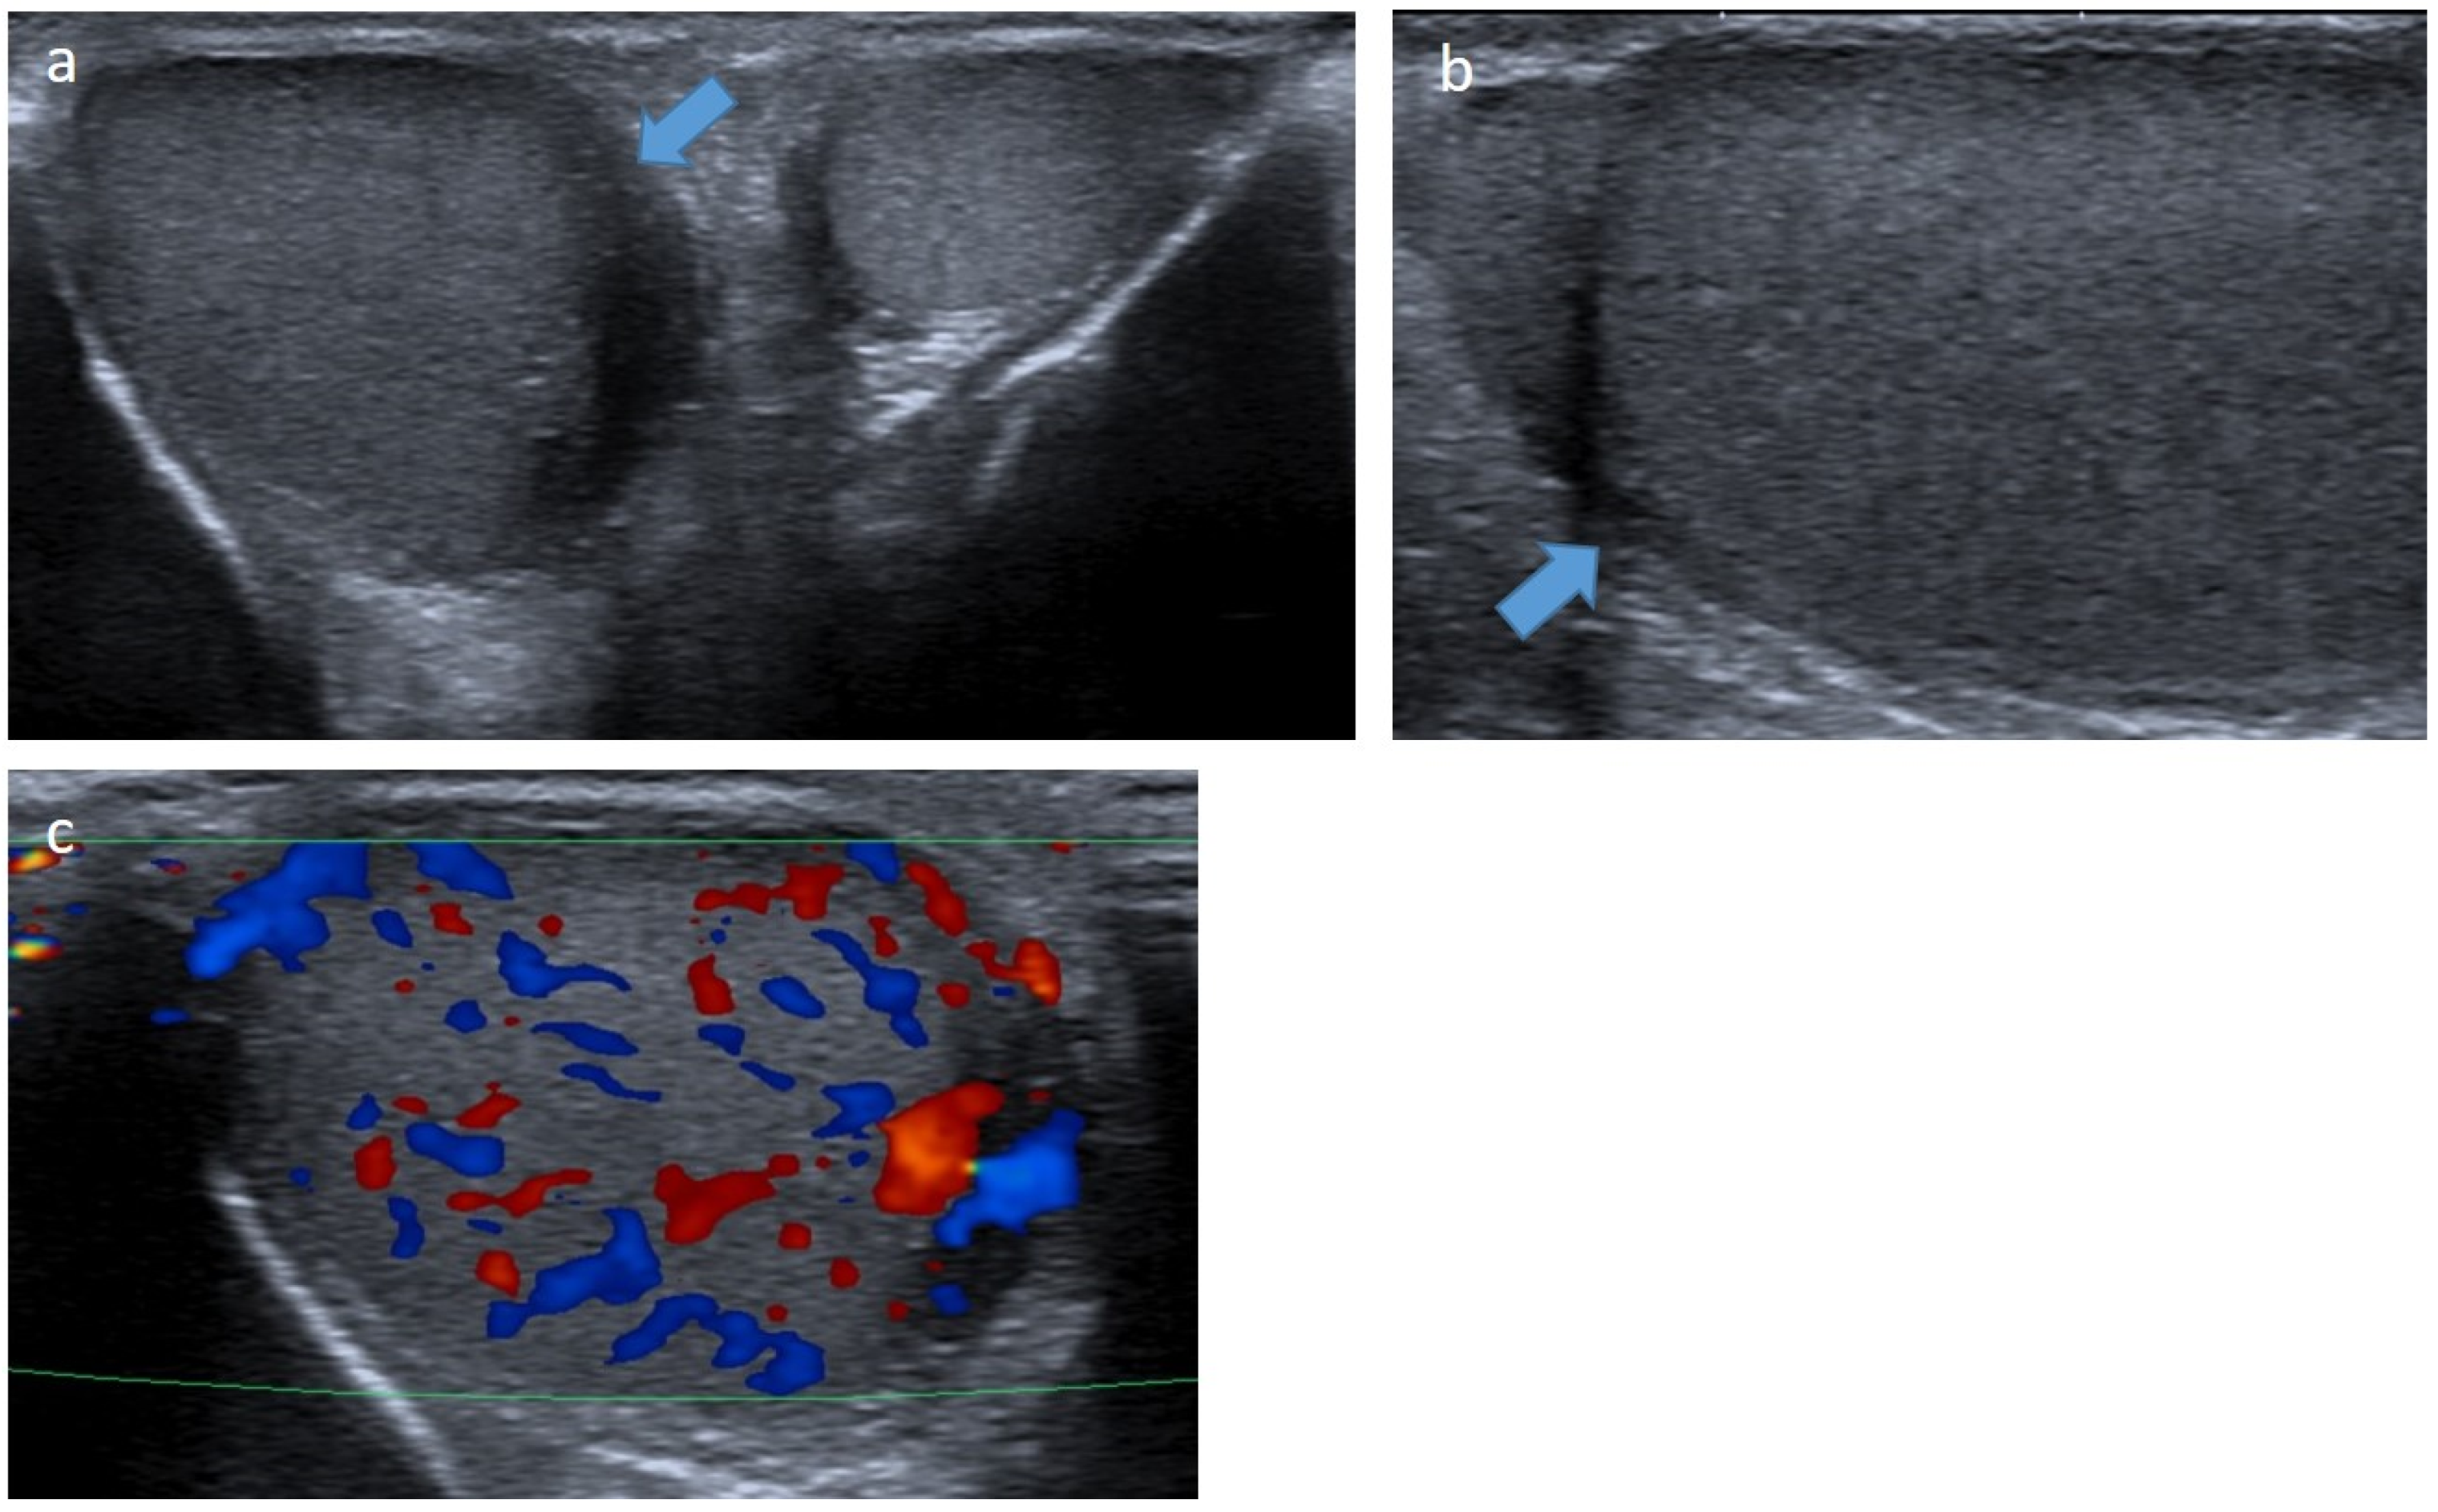

4.5.2. Sertoli-Cell Tumors

- Li, G.; Lee, M.S.; Kraft, K.H.; Heider, A. Prepubertal Malignant Large Cell Calcifying Sertoli Cell Tumor of the Testis. Urology 2018, 117, 145–149. [Google Scholar] [CrossRef]

- Ocal, O.; Baydar, D.E.; Idilman, I.S.; Dogan, H.S.; Tekgul, S.; Ozmen, M.N. Sonographic diagnosis of large-cell calcifying Sertoli cell tumor. J. Ultrason. 2019, 19, 161–164. [Google Scholar] [CrossRef]